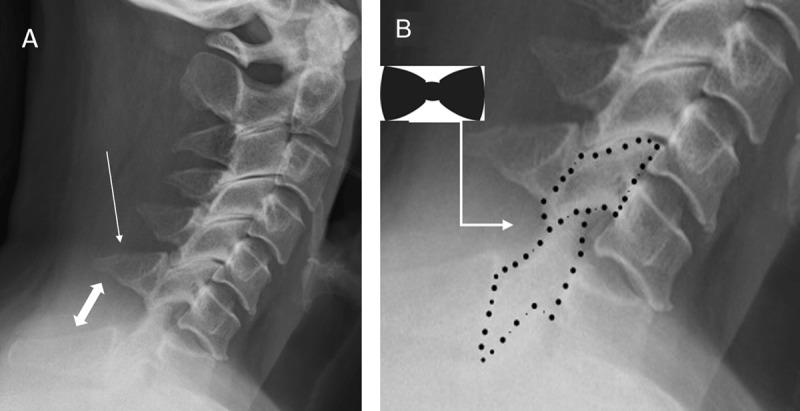

Unilateral cervical facet joint dislocation (UCFJD) is the most frequently missed cervical spine injury on plain radiographs. If left untreated, UCFJD can progress to bilateral cervical facet joint dislocation. Given the complexity of cervical facet joint dislocations, radiologists rely on metaphorical signs to identify them on radiographs. The "Bow-tie" and "laminar space" signs represent UCFJD on plain radiographs. The "reversed hamburger", "naked facet" and "headphones" signs represent cervical facet joint dislocations on axial cross-sectional imaging. Illustrating these signs in an engaging manner facilitates pattern-based recognition, which can benefit trainees and radiologists. Moreover, pattern-based recognition can be applied to machine learning.

单侧颈椎小关节脱位(UCFJD)是普通X线片上最常被漏诊的颈椎损伤。如果不进行治疗,UCFJD可进展为双侧颈椎小关节脱位。鉴于颈椎小关节脱位的复杂性,放射科医生依靠隐喻性征象在X线片上识别它们。“领结”和“椎板间隙”征象在普通X线片上代表UCFJD。“反转汉堡包”、“裸关节面”和“耳机”征象在轴向横断面成像上代表颈椎小关节脱位。以引人入胜的方式展示这些征象有助于基于模式的识别,这对实习生和放射科医生都有益。此外,基于模式的识别可应用于机器学习。